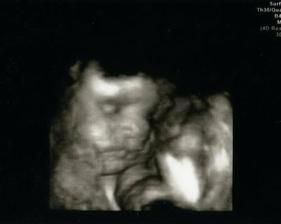

• 16.12. – první poradna v porodnici: sepsání papírů k porodu, monitor, prohlídka, UTZ (vážíme cca 2900 g), 36+4

• 7.1. – další poradna: už vážíme cca 3600 g, takže žádnej drobek to nebude. Ale prý to zas tak velký mimčo není (na moji výšku i s ohledem na cukrovku) a tak tomu necháme volnej průběh a vyvolávat se bude až po 10-12 dnech, kdyby to nešlo samo